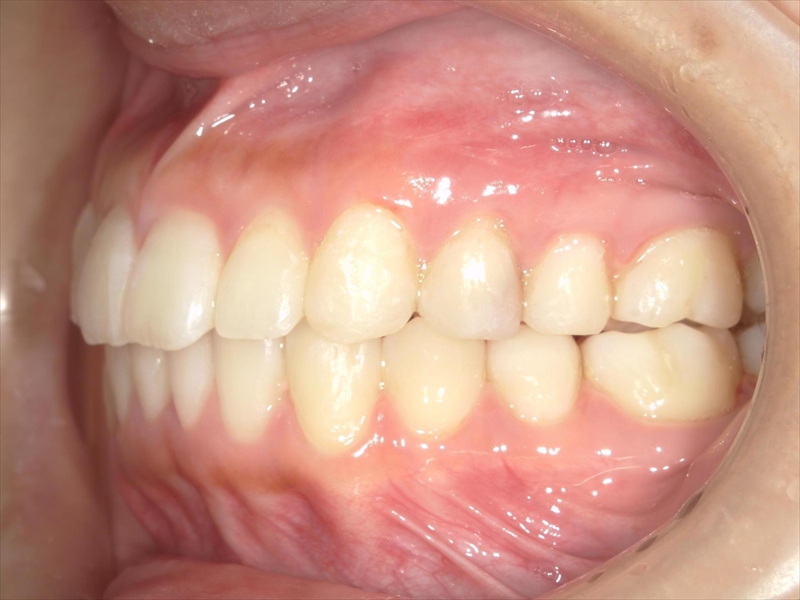

- 凄く綺麗になって嬉しい

治療前後 写真